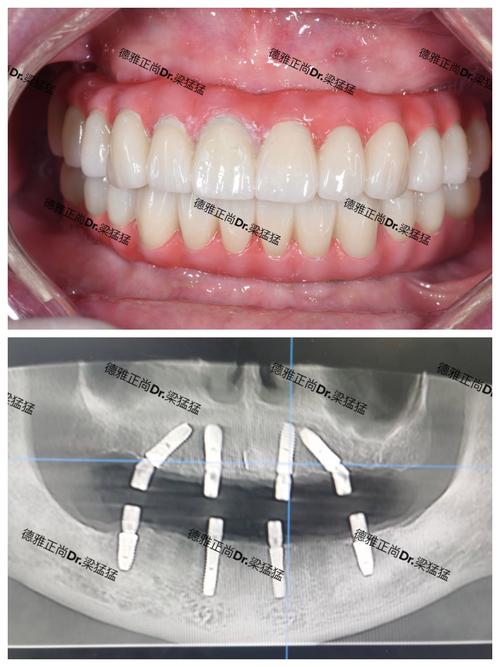

与活动假牙、固定桥等传统修复方式相比,种植牙被誉为“人类的第三副牙齿”,其核心优势在于“独立扎根、功能媲美真牙”,种植牙是通过外科手术将纯钛种植体植入牙槽骨,作为人工牙根,待其与骨组织结合后,再安装牙冠,这一过程不仅能恢复牙齿的咀嚼功能,更能刺激牙槽骨避免萎缩,保护邻牙健康。

- All-on-4半口/全口种植:针对多颗或半口、全口缺牙的母亲,通过植入4颗种植体支撑整排牙冠,避免大量植骨,创伤小、费用相对较低,且恢复后咀嚼功能接近真牙。